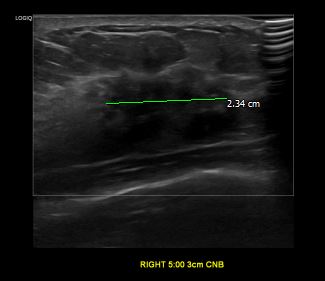

상기환자 우측 만져지는 멍울로 정밀검사위해 내원하신 40대 여성분으로

우측유방 혹 총조직검사 시행해 유방암 진단되었습니다